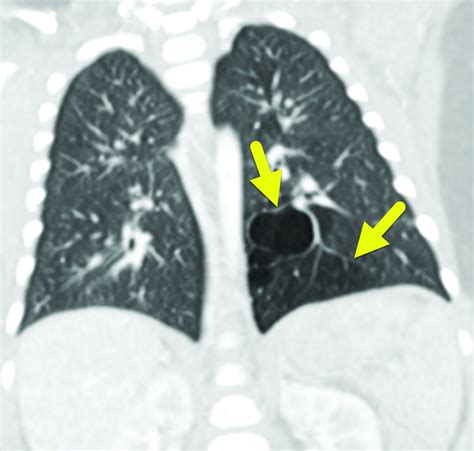

Diagnosing Congenital Pulmonary Airway Malformations (Cpam) typically involves a combination of prenatal and postnatal evaluations. Prenatal diagnosis is often made through ultrasound or magnetic resonance imaging (MRI), which can detect abnormalities in the fetal lungs. Postnatal diagnosis may involve chest X-rays, computed tomography (CT) scans, or MRI to confirm the presence and type of Cpam.

• Type 1 Cpam: This is the most common type and is characterized by large cysts that can compress adjacent lung tissue.

• Type 4 Cpam: This type is characterized by large, thin-walled cysts and is often misdiagnosed as a pleural effusion.